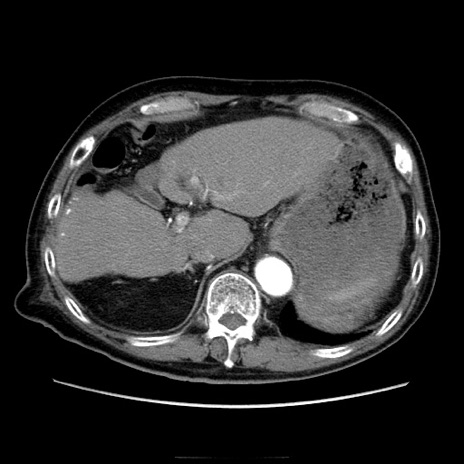

症例21(横断像)

【症例】70歳代男性

【主訴】腹痛

【現病歴】肝硬変・肝細胞癌にてかかりつけの方。約9時間前に食後より腹痛出現。症状が徐々に増悪し、嘔吐出現したため来院。

【既往歴】肝硬変、肝細胞癌(RFA、TACE後)

【身体所見】意識清明、表情苦悶様、BT 36℃、BP 129/78mmHg、P 88bpm、SpO2 97%(RA)、右上腹部から心窩部にかけて圧痛あり、反跳痛なし、筋性防御あり。

【データ】WBC 5800、CRP 0.16